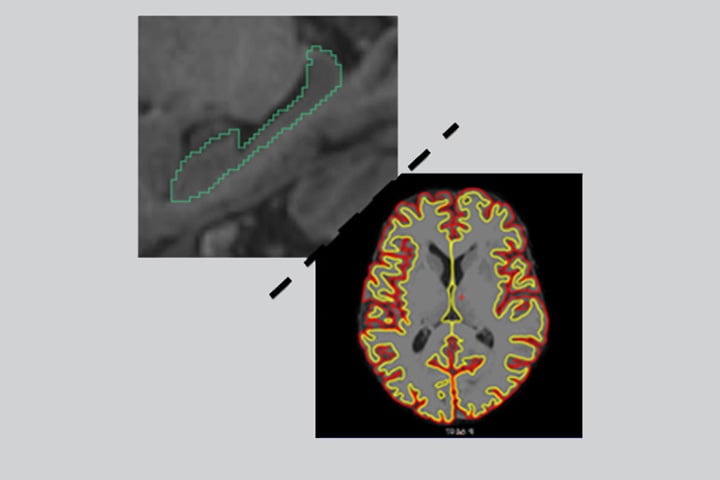

Des travaux récents en IRM structurelle ont suggéré que la catégorisation de l’atrophie cérébrale en sous-types caractéristiques permettait d’identifier des présentations biologiquement et cliniquement différentes de maladie d’Alzheimer (MA). Cette catégorisation pourrait servir de marqueur de substitution de la distribution de la tauopathie dans la MA selon les résultats d’étude comparant les données IRM avec la TEP-tau ou la neuropathologie post-mortem. On distingue ainsi 4 grands sous-type d’atrophie: l’atrophie « diffuse/typique », l’atrophie « limbique-prédominante », l’atrophie « épargnant l’hippocampe » et l’atrophie « minime ». Cependant, les études précédentes portaient sur des échantillons de patients très sélectionnés : présentant des biomarqueurs amyloïdes positifs, atteints de troubles cognitifs légers (MCI) amnésiques ou bien atteints de démence de type Alzheimer. Ainsi, l’intérêt clinique de cette analyse en imagerie restait encore inconnu dans une population reflétant la grande variété des présentations cognitives vues dans les centres mémoire.

Ils ont constaté que le pattern d’atrophie « typique/diffus » était associé à un déclin cognitif plus rapide et au risque le plus élevé de développer une démence en particulier de type MA au cours du suivi, à la fois dans l’ensemble de l’échantillon analysé et chez les participants pour lesquels le statut amyloïde positif était connu. Les atrophies « limbique-prédominante » et « épargnant l’hippocampe » ont également été associées à une incidence des démences plus élevée durant les 4 ans de suivi, avec un déclin cognitif plus rapide dans le groupe « limbique-prédominant ». La démence à corps de Lewy était plus fréquente dans les groupes de patients présentant une atrophie « épargnant l’hippocampe » ou une atrophie « minime ». Les auteurs ont conclu que la catégorisation en sous-types d’atrophie cérébrale pourrait être largement utilisée comme biomarqueur pour fournir des informations précieuses dans la pratique clinique et des critères utiles au développement d’essais cliniques pour identifier les sous-groupes de patients « progresseurs rapides ».